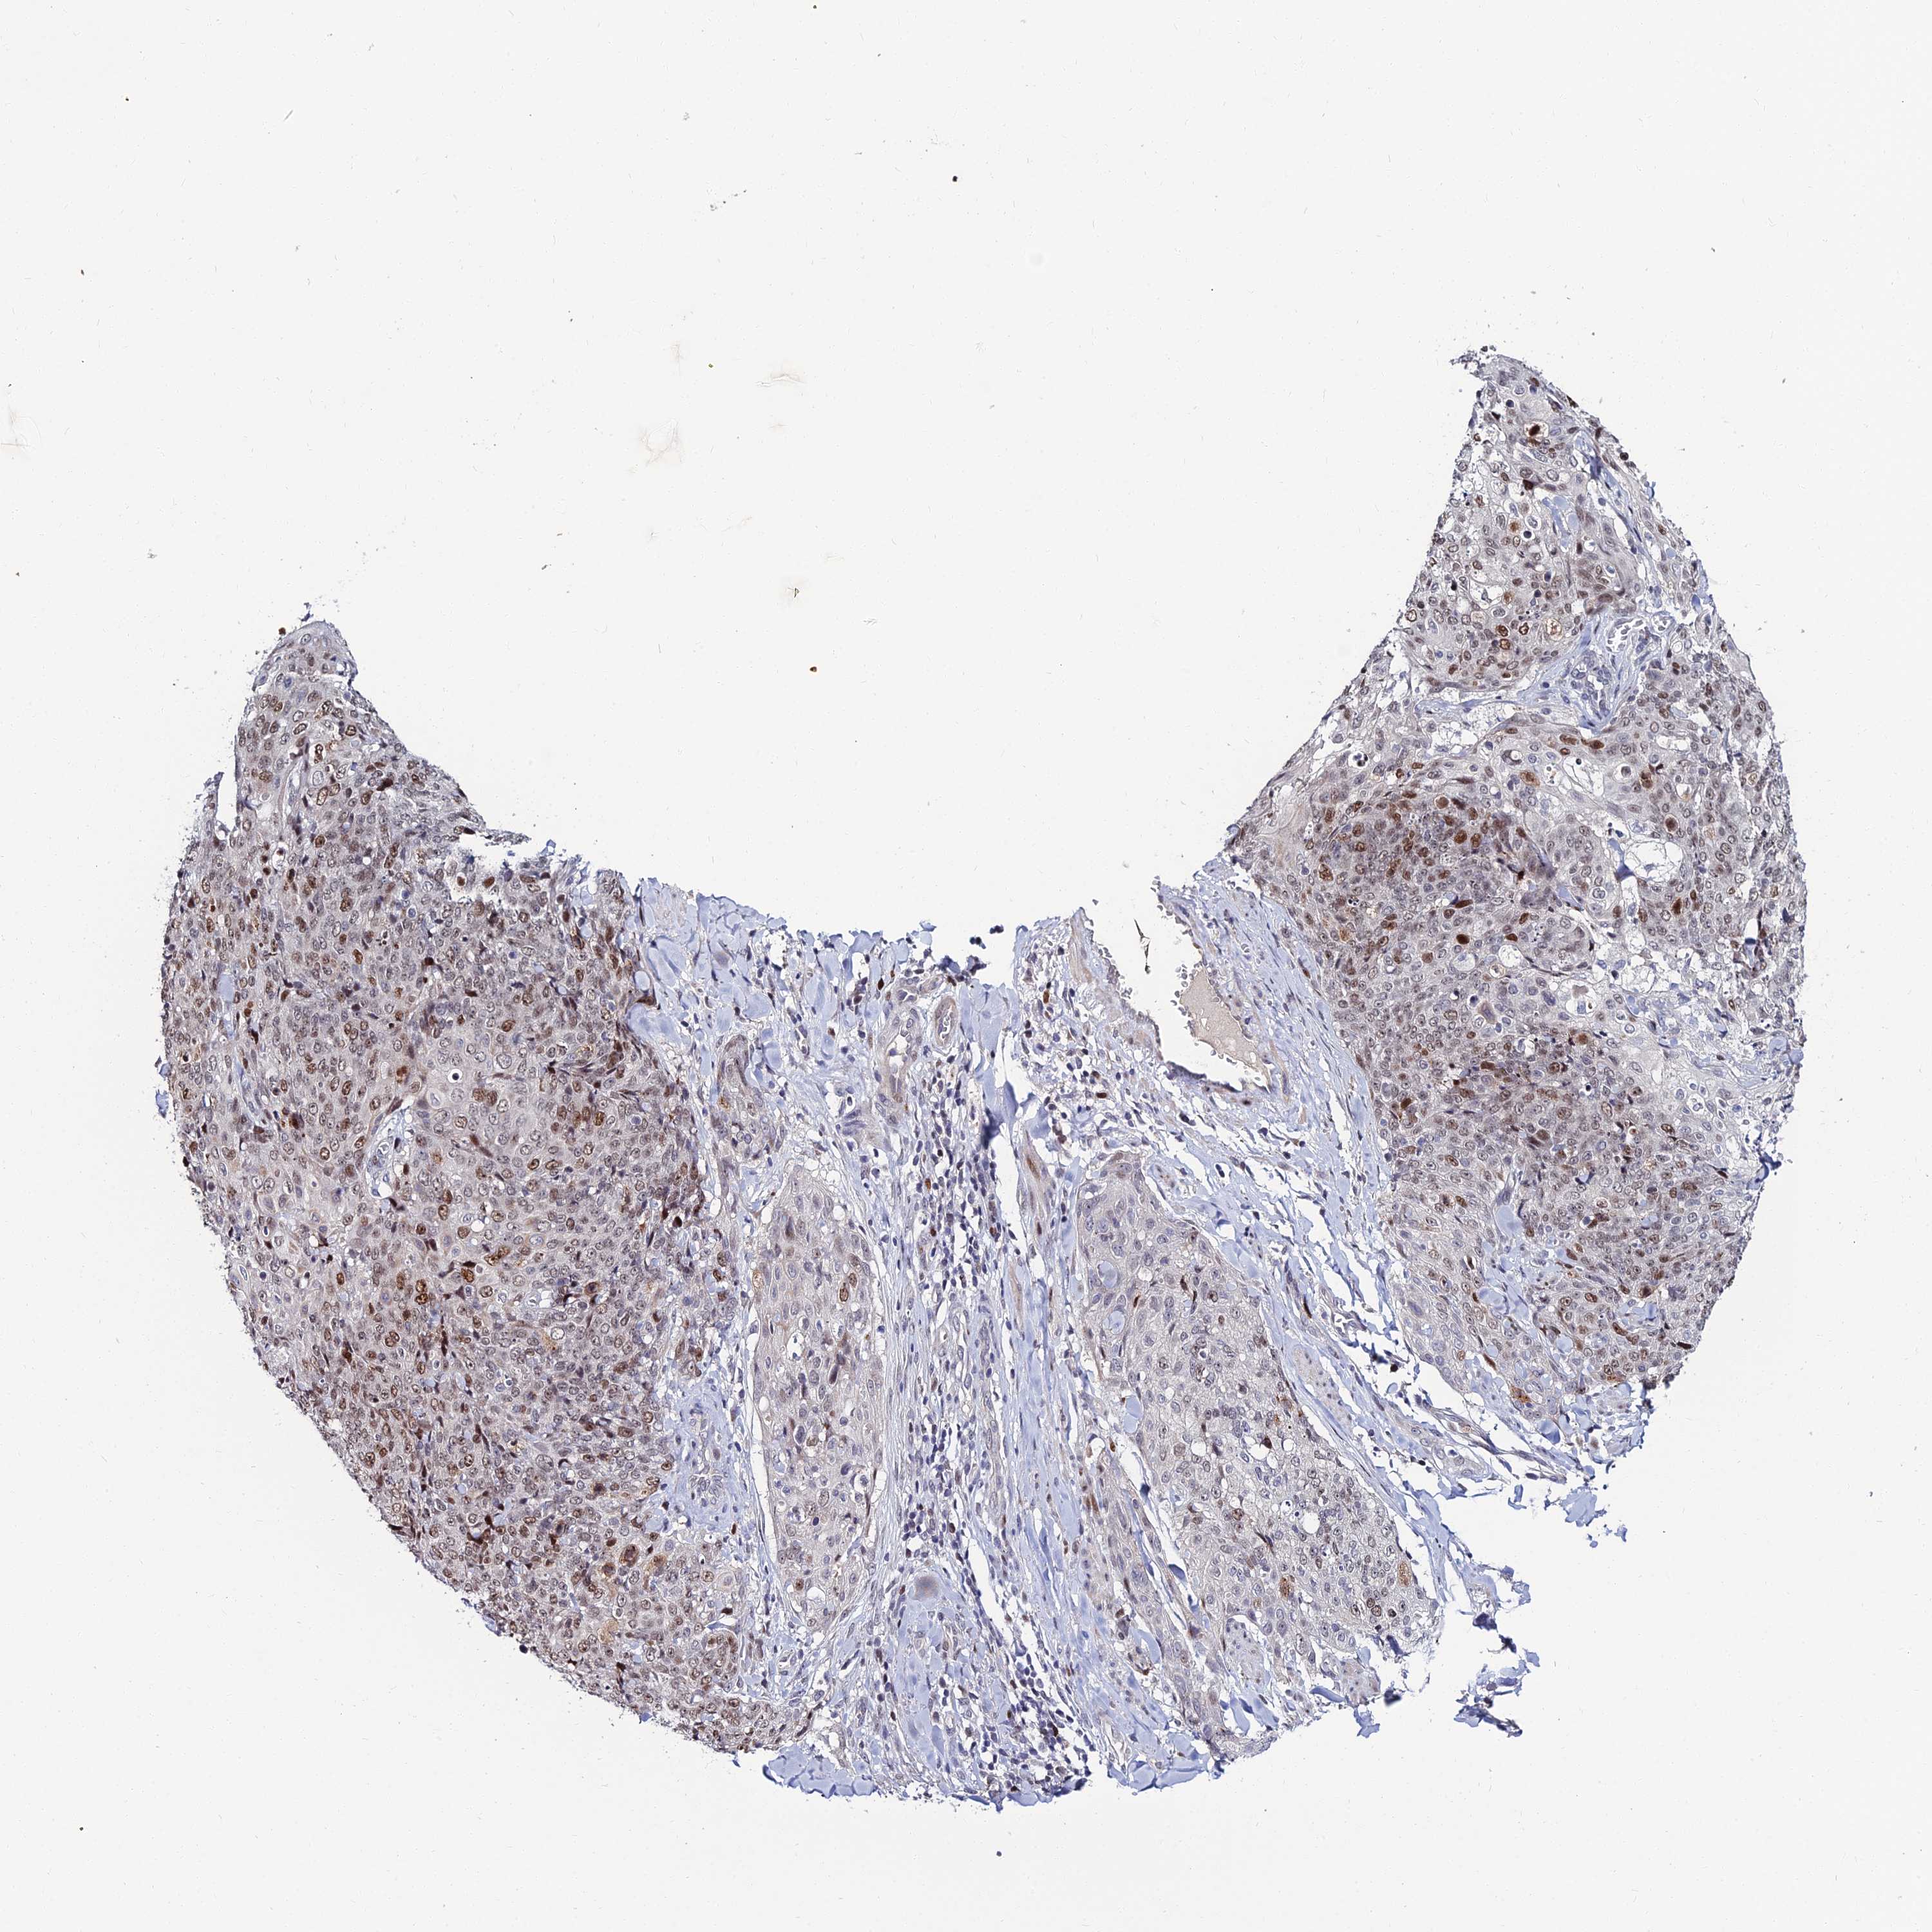

SKIN CANCER - Protein expressioni

A mouse-over function shows sample information and annotation data. Click on an image to view it in a full screen mode. Samples can be filtered based on level of antibody staining by selecting one or several of the following categories: high, medium, low and not detected. The assay and annotation is described here.

Antibody stainingi

Antibody staining in the annotated cell types in the current human tissue is reported as not detected, low, medium, or high, based on conventional immunohistochemistry profiling in selected tissues. This score is based on the combination of the staining intensity and fraction of stained cells.

Each image is clickable and will lead to virtual microscopy that enables deeper exploration of all samples and also displays staining intensity scores, fraction scores and subcellular localization as well as patient and tissue information for each sample.

Antibody HPA045275

Staining

High

Intensity

Strong

Quantity

>75%

Location

Nuclear

Basal cell carcinoma